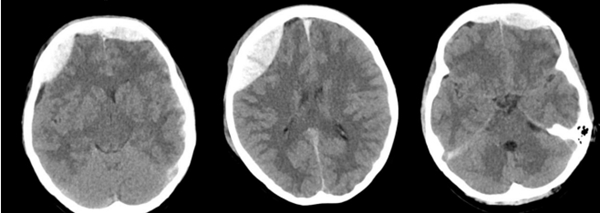

2025年10月29日是第20个“世界卒中日”,今年的主题是:“尽早识别、立刻就医”。为提升全民对脑卒中的防治意识,做到早预防、早发现、早治疗,中山大学附属第一医院(简称中山一院)广西医院积极响应号召,组织多学科专家开展脑卒中防治的义诊活动。当天上午,本次义诊团队由我院副院长、神经外科学科带头人杨超教授,神经内科主任欧紫琳、副主任吴月娟,营养科执行主任陆光成,以及神经外科梁有明副主任医师、...